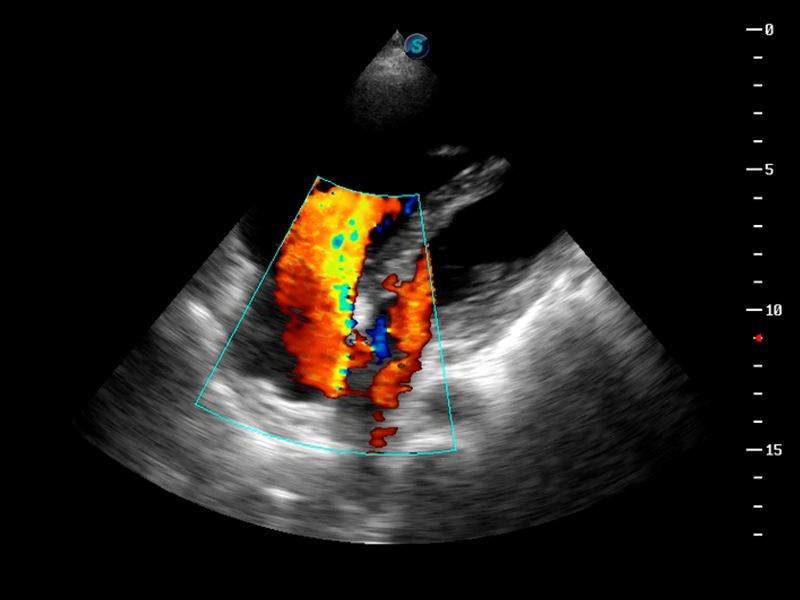

S9便携式彩色多普勒超声诊断仪是竞技宝(JJB)官方网站研发的高端便携彩超设备,外观设计新颖、产品性能卓越。S9在便携超声领域采用了突破传统的触摸屏交互设计,并以先进的软件硬件技术和设计理念,为您带来清晰的图像质量、稳定的工作性能和便捷的操作体验。

TDI组织多普勒成像